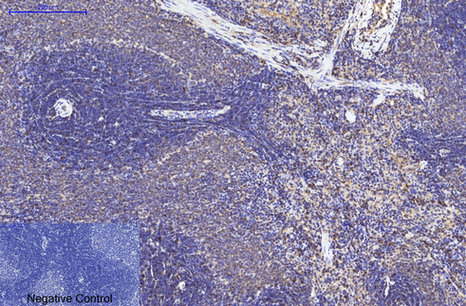

ARG66176 anti-eIF4A1 antibody IHC-P image

Immunohistochemistry: Paraffin-embedded Rat spleen tissue stained with ARG66176 anti-eIF4A1 antibody at 1:200 dilution (4°C, overnight). Antigen Retrieval: Boil tissue section in Sodium citrate buffer (pH 6.0) for 20 min.

Negative control was used by secondary antibody only.